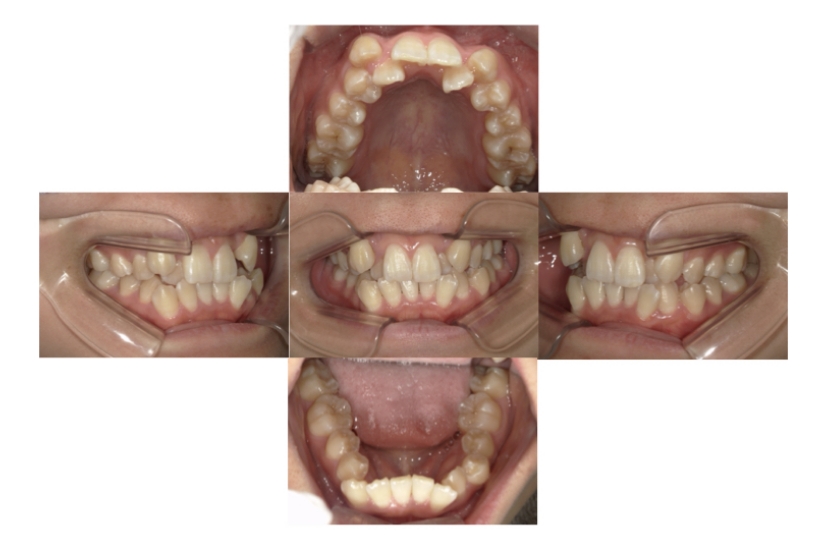

症例1

上顎前突、叢生

抜歯

ブラケット矯正

上下顎叢生、上顎前突(出っ歯、上下の前歯のガタガタ)のケースです。

装置はラビアル(上下表側)で、上顎の小臼歯を2本抜歯を行っています。抜歯したスペースを使って、上の前歯の後方移動と叢生(ガタガタ)と出っ歯の改善を行っています。下は歯と歯の間にIPR(隣接面削合)を行い、スペースを確保し、叢生の改善を行っています。

主訴 前歯のガタガタと出っ歯が気になる。

年齢・性別 47歳 女性

お住まいの地域 神奈川県川崎市

治療方針 抜歯スペースおよびIPRを利用して上前歯の叢生(ガタガタ)の改善

抜歯部位 上顎左右第一小臼歯

使用装置 ラビアル(上下表側)、顎間ゴム

治療期間 2年0か月

治療回数 15回

リテーナー クリアリテーナー

BEFORE